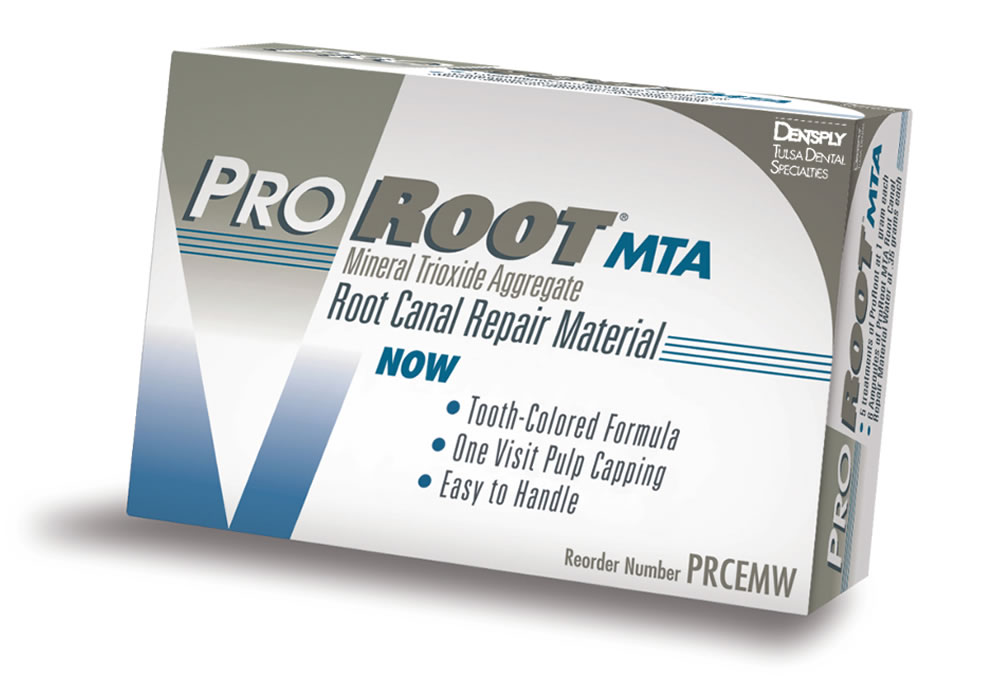

殺菌性と修復機能のMTAセメント

細菌物質を除去した後は、根管充填と呼ばれる根管内の空洞を埋める処置が必要となり、隙間なく埋める事で再発を抑える事ができるため、とても重要な処置となります。

細菌物質を除去した後は、根管充填と呼ばれる根管内の空洞を埋める処置が必要となり、隙間なく埋める事で再発を抑える事ができるため、とても重要な処置となります。

当院では、MTAと呼ばれる殺菌効果のある歯科用セメントで根管充填を行い、根管内部の徹底殺菌と緊密な封鎖を行っています。

根の中の消毒が終わったら、最終的な薬を詰めて根の中の空洞を封鎖する根管充填(こんかんじゅうてん)を実施。

MTAというセメントを根の中に詰めていきます。MTAセメントは殺菌したり、歯を再生させたり、穴の空いた歯の部分を埋めたりすることのできる新しい薬です。

MTAというセメントを根の中に詰めていきます。MTAセメントは殺菌したり、歯を再生させたり、穴の空いた歯の部分を埋めたりすることのできる新しい薬です。

通常、殺菌力の強い薬は歯や周りの組織に対しても悪い影響を与えますが、MTAセメントは体の組織に適度な刺激を与え、悪くなってしまった部分を再生させる作用があるお薬です。